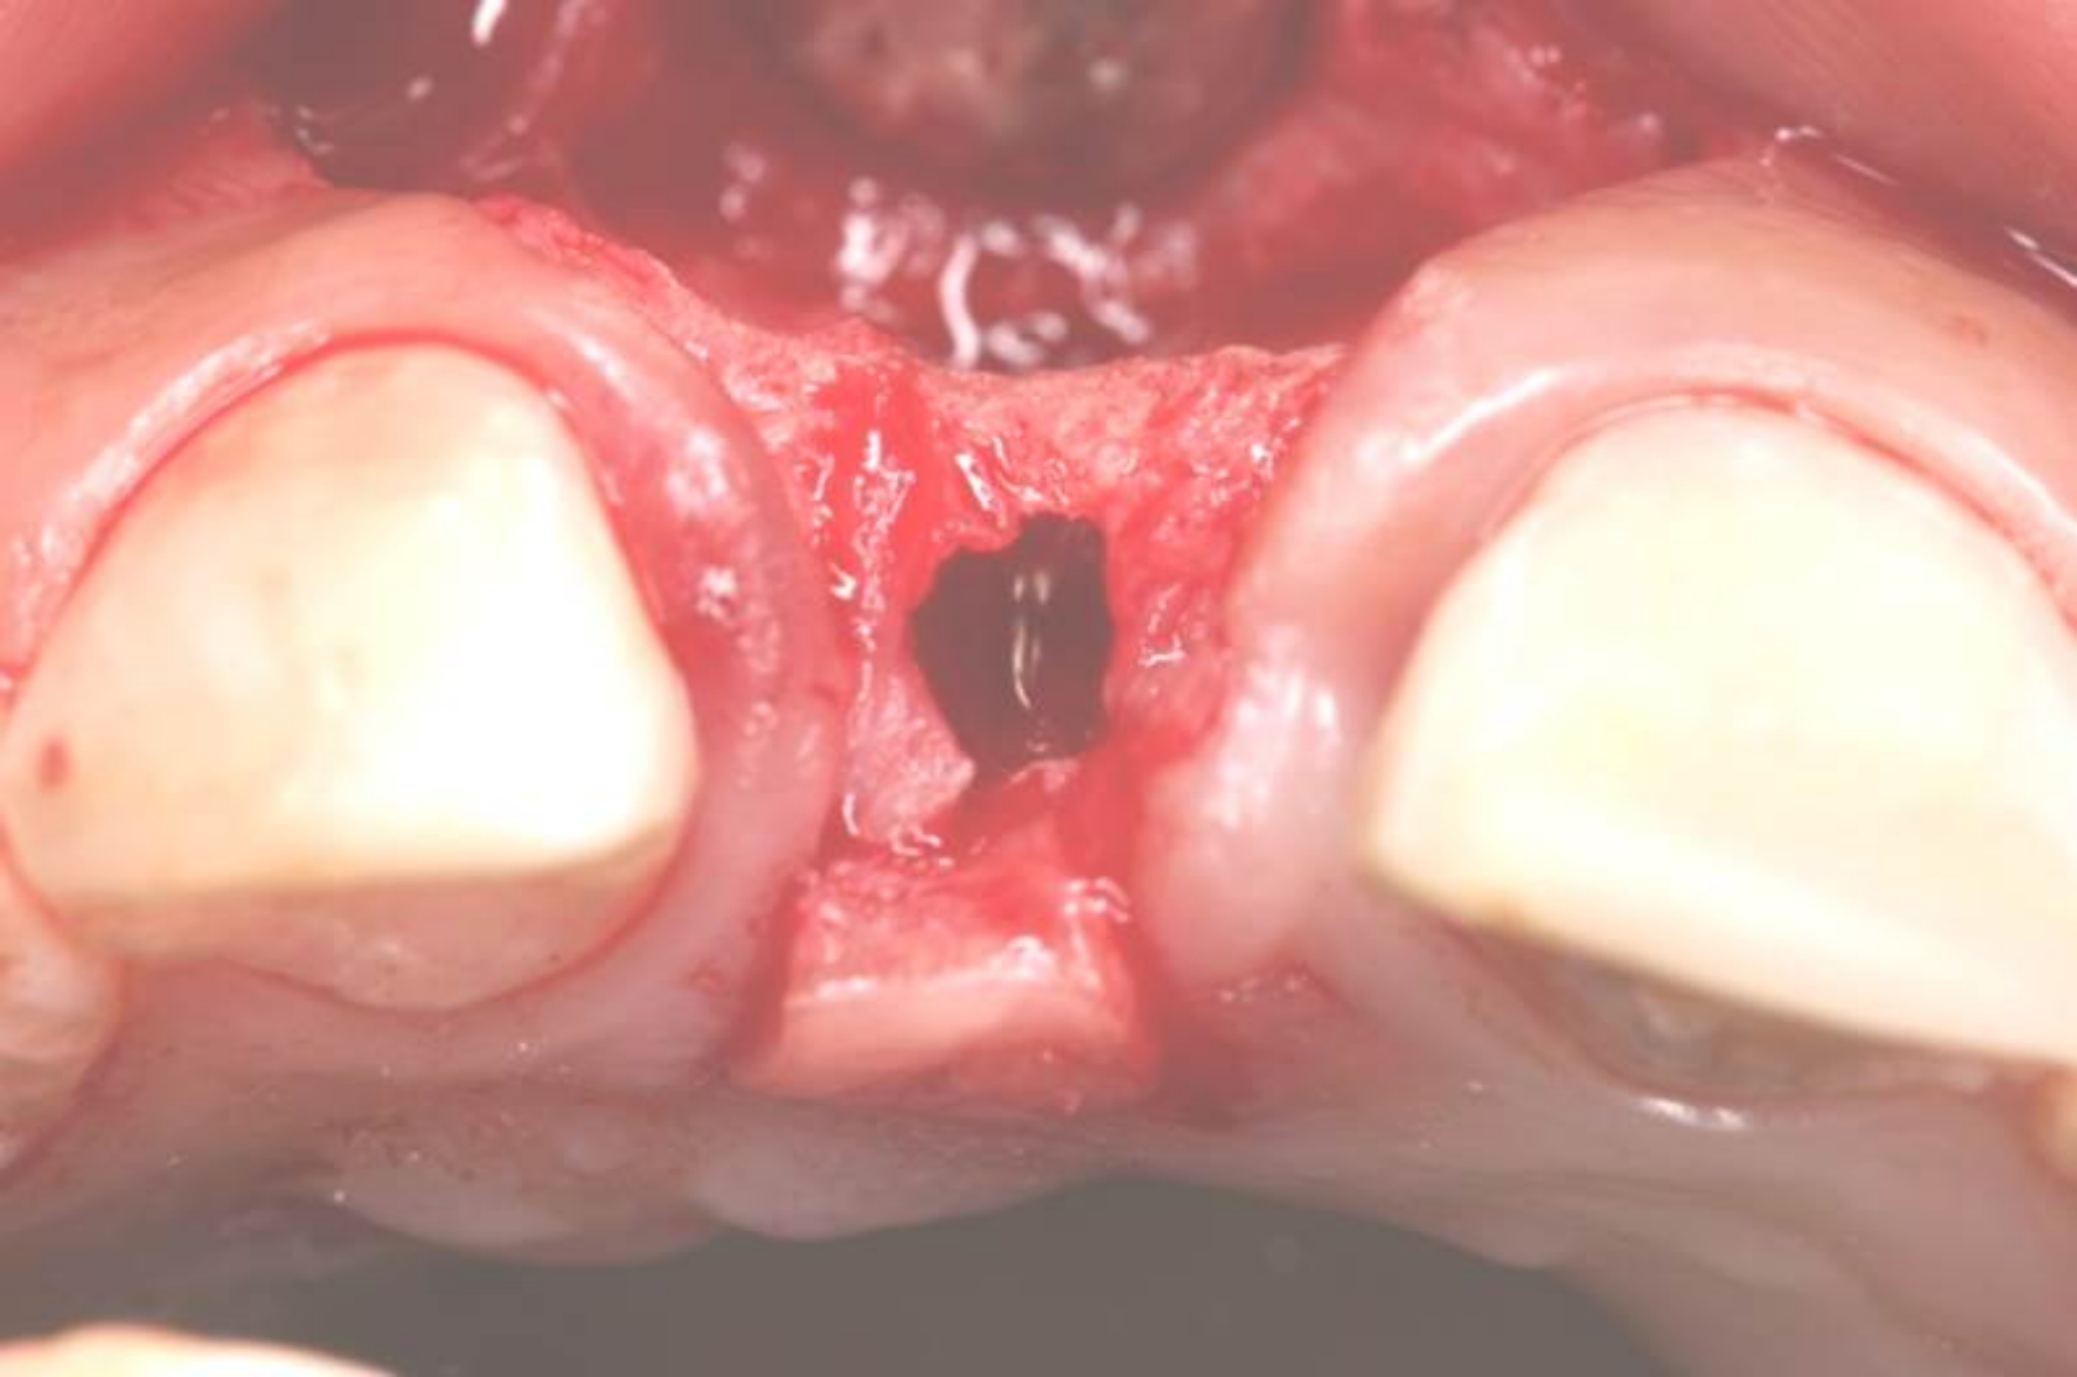

Fig 13. A buccal pedicle flap was elevated, exposing the buccal bony plate.

Figure 13